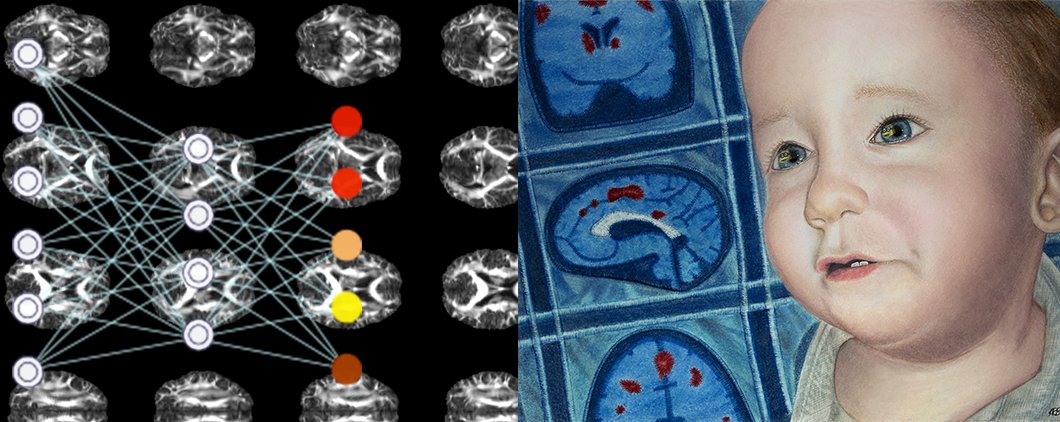

I am delighted to say that our paper was recently accepted and published by Glia. Thank you to everyone who played a part in getting this paper together, it was a privilege to work with you all! Sarah McComish Maeve Caldwell